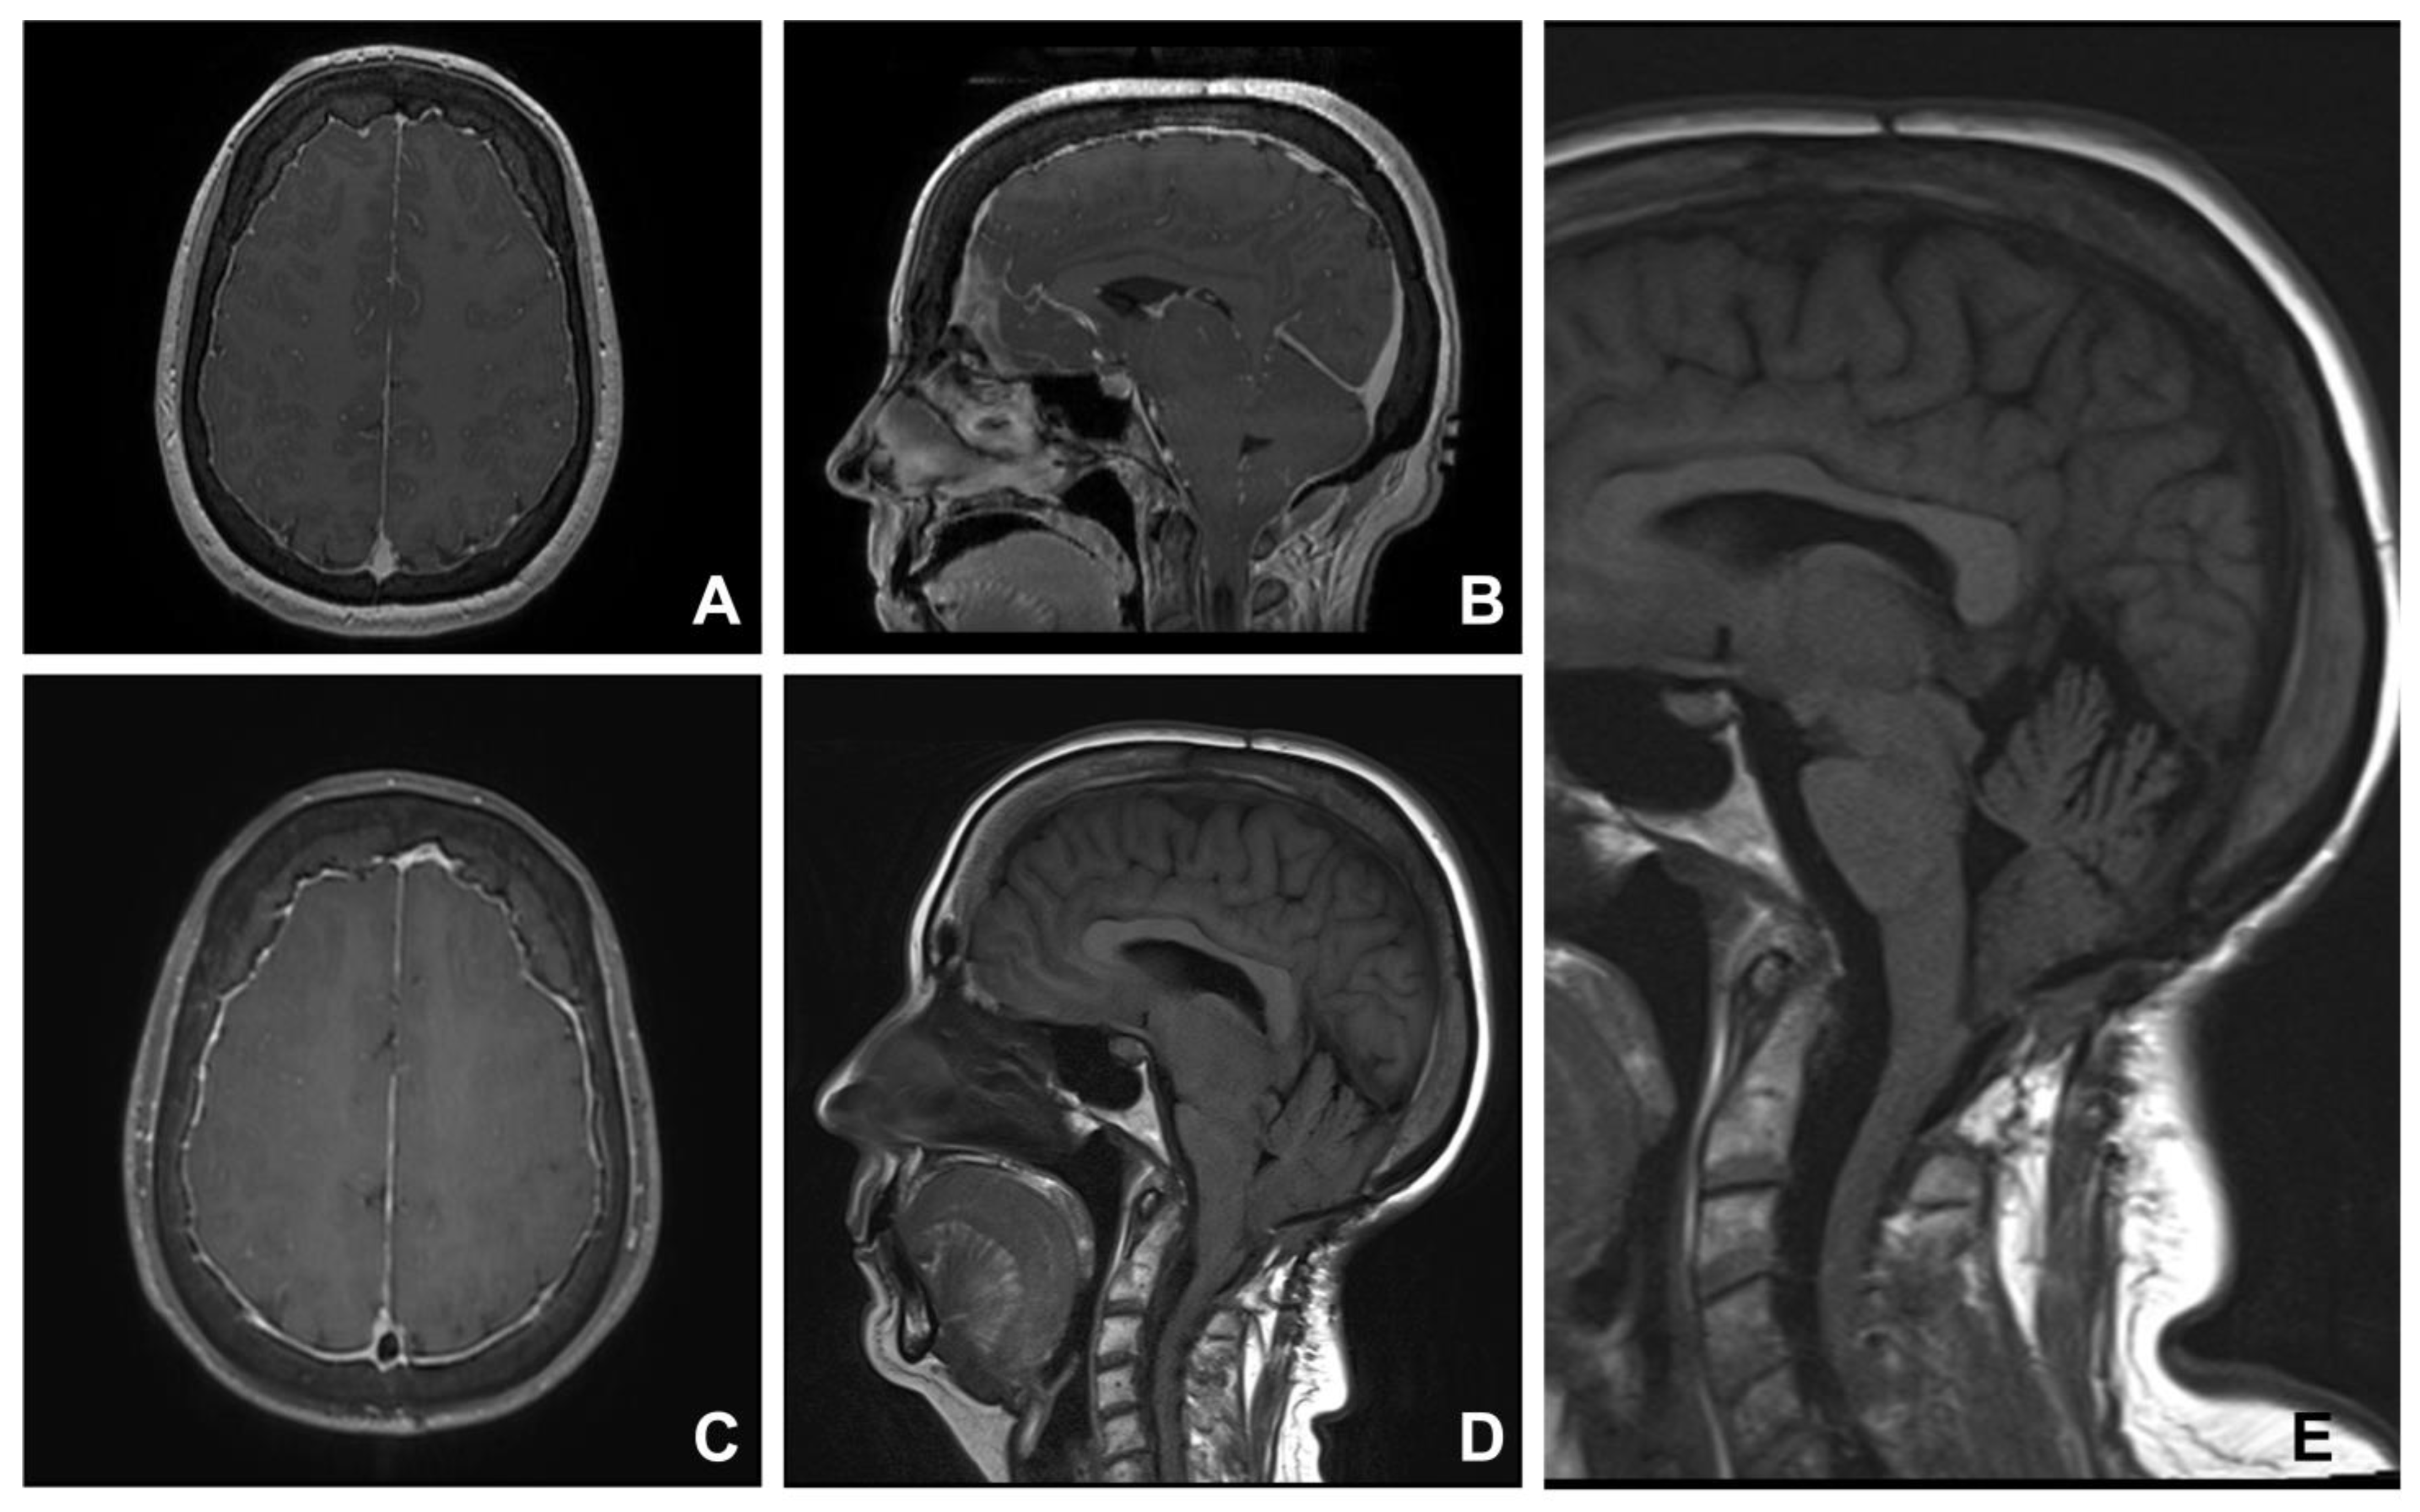

Understand the implications of cerebral tonsils low lying, a condition often linked to Chiari malformation. Discover the common symptoms, diagnostic MRI procedures, and modern treatment options for cerebellar descent. Learn how this structural brain anomaly affects your health and when to consult a neurologist for expert management of your neurological symptoms.

TitleChiari Malformation Types 1 4

Read full article: Cerebral Tonsils Low Lying